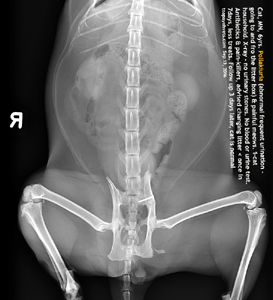

DIAGNOSIS - X-RAYS